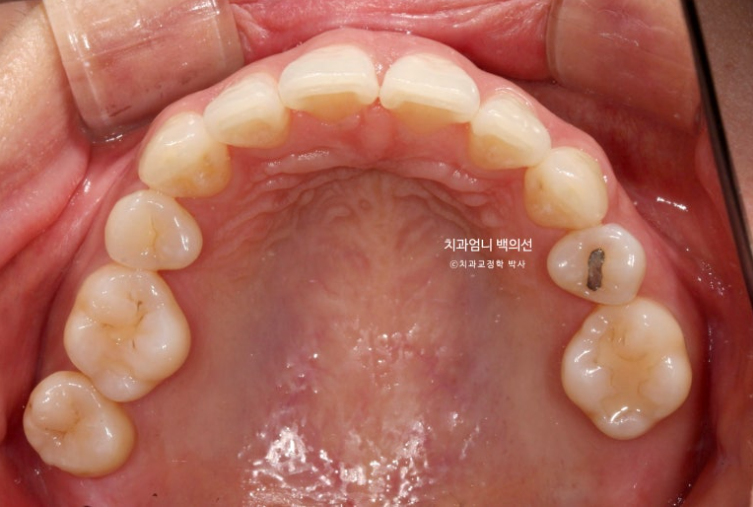

오래 전 했던 발치교정으로 작은어금니 4개가 없는 상태인데 좌측 첫번째 큰어금니 1개가 추가로 더 없습니다.

상악 좌측에만 치아갯수가 2개나 없는 것 입니다.

엑스레이상 좌측 위 첫번째 작은어금니쪽으로 두 번째 작은어금니가 쓰러지며 공간이 없어진 것이 보입니다.

어금니 교합관계는 2급입니다.